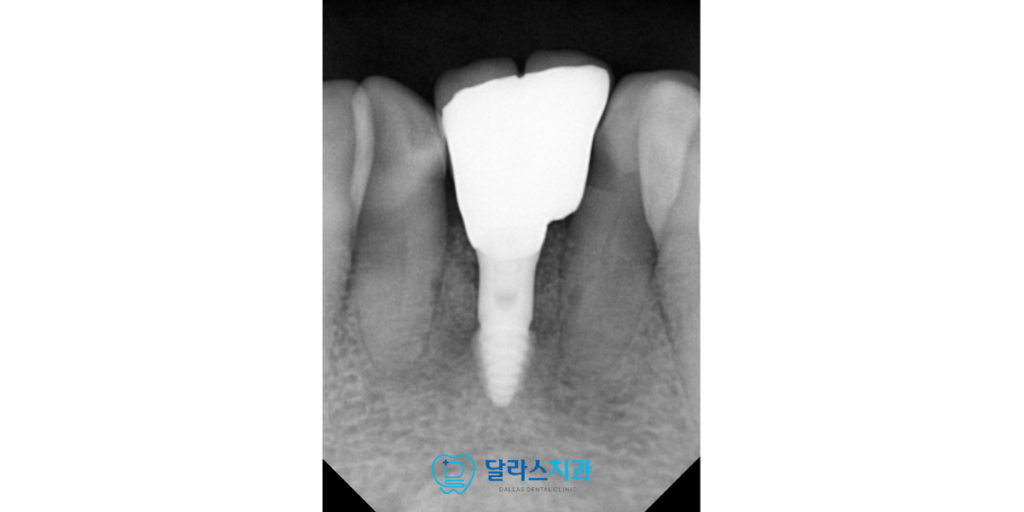

노원치과 치료는 문제가 발생한 두 개의 치아를 발치함과 동시에

즉시 임플란트를 식립하는 방식으로 진행되었습니다.

이때 부족한 지지력을 보강하고

보철물이 안정적으로 자리 잡을 수 있도록

치조골 이식술을 병행하였습니다.

이는 임플란트가 잇몸 뼈와 단단하게 결합할 수 있는

토대를 만들어주는 중요한 과정입니다.

최종 보철물을 장착한 날 확인한 결과

임플란트를 단 한 개만 식립하였음에도 불구하고

앞니 부위의 복잡했던 치아 배열이 깔끔하게 변화했습니다.

치료 후 2025.11.26